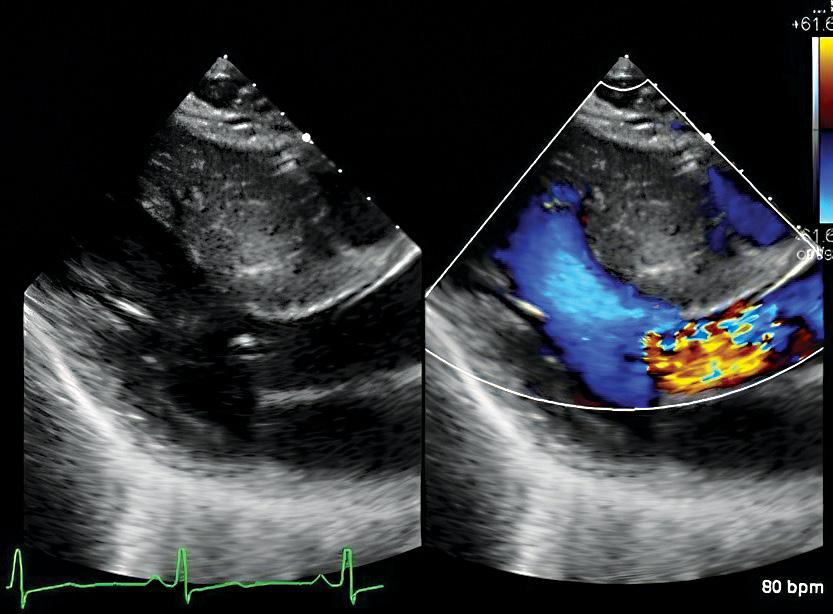

Transthoracic echocardiography showing systolic anterior motion of the mitral valve due to HCM.

Transthoracic echocardiography (TTE) is the first-line diagnostic test in the evaluation of HCM. TTE is not specific for the diagnosis of HCM but it helps exclude other structural abnormalities that cause increased LV wall thickness, including a subaortic membrane and aortic valve stenosis. TTE findings typical of HCM include increased LV wall thickness, systolic anterior motion of the mitral valve, LV outflow tract obstruction (LVOTO), abnormal diastolic function and abnormal myocardial deformation or strain. CMR is usually performed following an abnormal TTE indicative of HCM.

A crucial step in the characterization and management of HCM is to establish the presence or absence of LVOTO, which is not always seen on examinations at rest. Exercise stress echocardiography (SE) is performed to show presence of provokable LVOTO, assess hemodynamic response to exercise and objectively define a person’s exercise capacity. In individuals with obstructive HCM, SE guides treatment recommendations and allows monitoring of therapeutic effects.